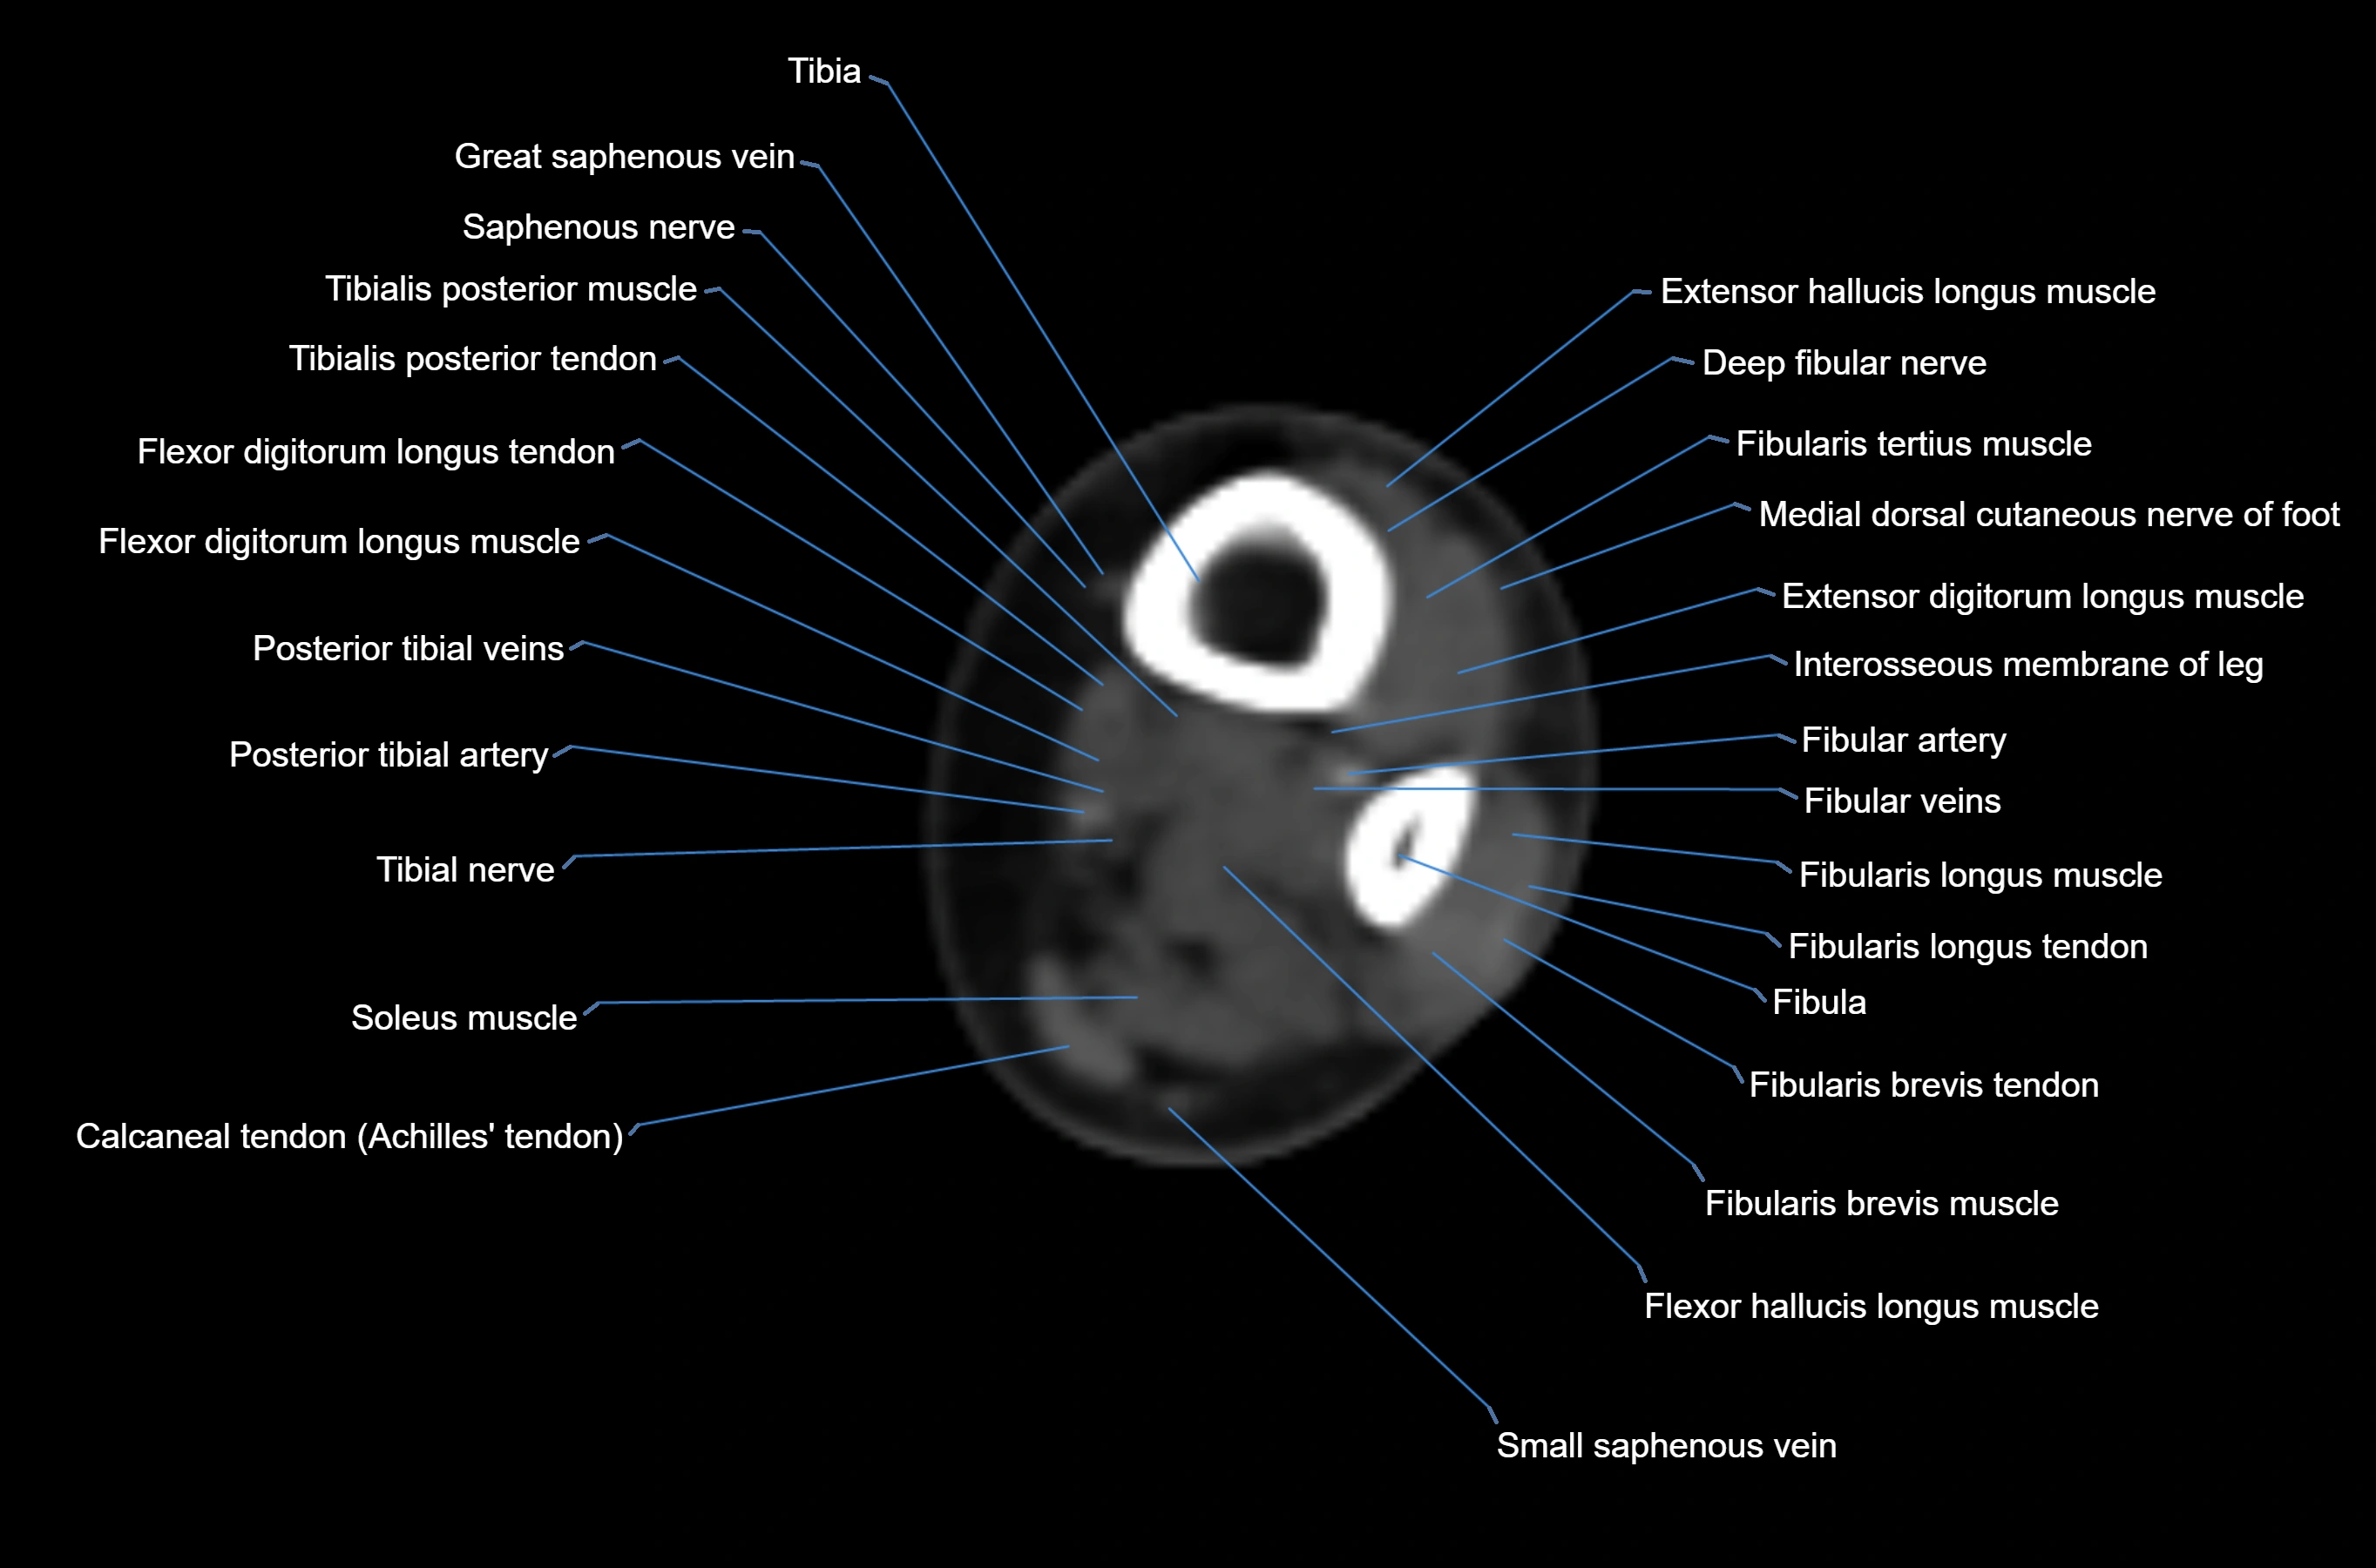

MRI image

CT image